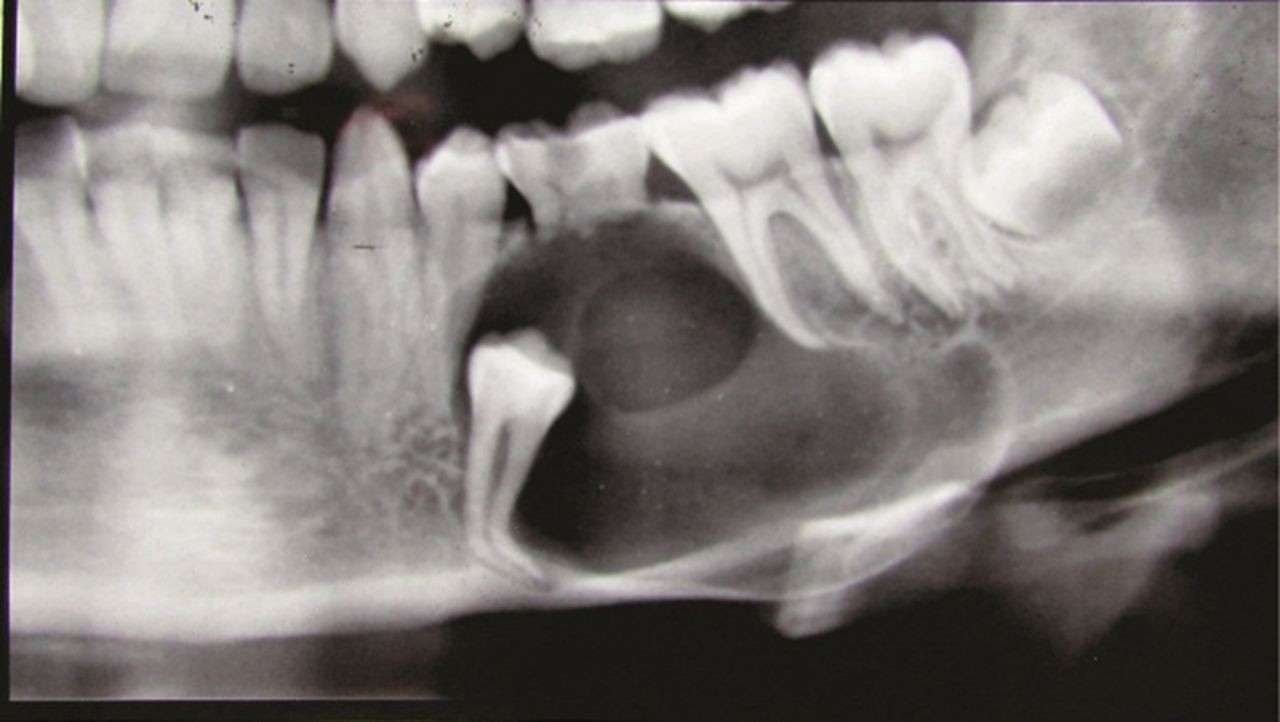

Dentigerous cysts are the second most common type of odontogenic cyst, which is a fluid-filled sac that develops in the jaw bone and soft tissue. They form over the top of an unerupted tooth, or partially erupted tooth, usually one of your molars or canines. While dentigerous cysts are benign, they can lead to complications, such as infection, if left untreated.

How is it diagnosed?

Small dentigerous cysts often go unnoticed until you have a dental X-ray. If your dentist notices an unusual spot on your dental X-ray, they may use a CT scan or MRI scan to make sure it’s not another type of cyst, such as a periapical cyst or an aneurysmal bone cyst.

In some cases, including when the cyst is larger, your dentist may be able to diagnose a dentigerous cyst just by looking at it.